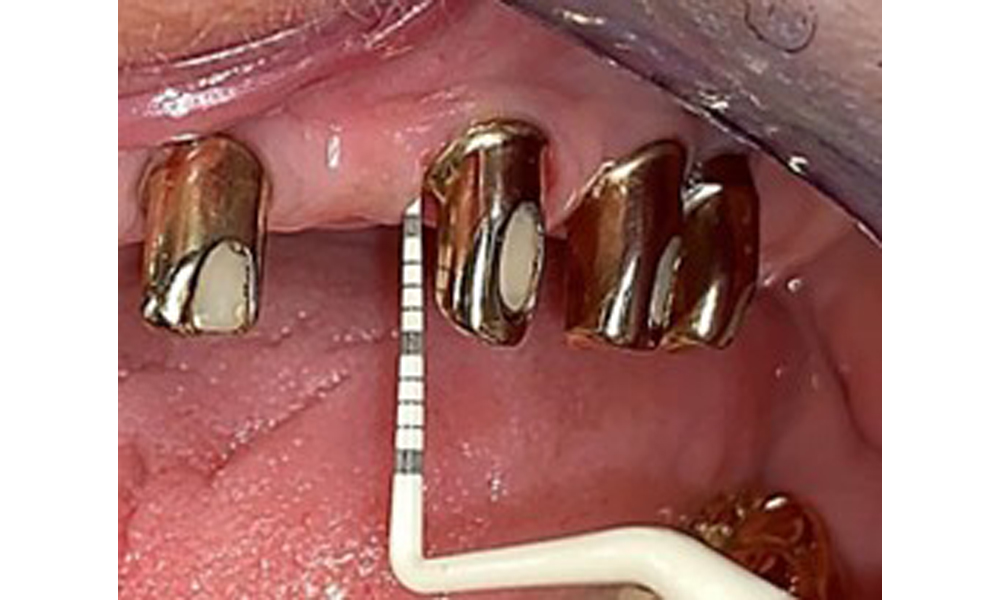

Based on the medical history, the risk of complications is classified as mild to moderate due to the intake of ASA 100 and bisoprolol. It should be noted that increased bleeding may occur during treatment, particularly if gingivitis is present. The risk is classified as low in the present case, as the patient maintains excellent intraoral hygiene. Due to the otherwise stable intraoral status over many years, the needs determined during the intraoral examination will be decisive for her treatment. The findings observed during any dental appointment will determine the subsequent course of treatment. Determination of bleeding status is mandatory to detect gingival changes in peri-implant tissues (Fig. 6).

Probing implant 23 at a probing depth of 4 mm using a plastic probe, showing negative BOP findings and a hyperplastic papilla.

Fig. 6: Probing implant 23 at a probing depth of 4 mm using a plastic probe, showing negative BOP findings and a hyperplastic papilla.

The periodontal status should be thoroughly examined once a year. This examination provides comprehensive documentation of the periodontal and implant findings, including pocket depths, periodontal recession and furcation involvement. This will ensure a rapid response to any potential progression of the mucositis, gingivitis, periodontitis or peri-implantitis. Implant probing using a plastic probe is recommended. In the present case, a mesial probing depth of 4 mm was detected mesial to implant 23. No suppuration or bleeding was detected, indicating the absence of peri-implantitis.